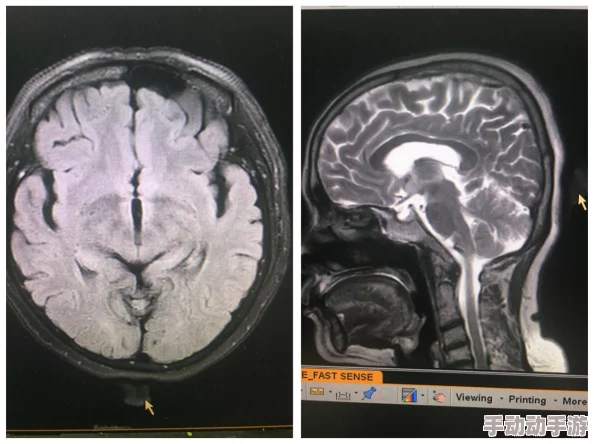

为了降低黄色综合症的误诊率,提高早期筛查显得尤为重要。医学专家建议,在出现相关症状时,应进行全面检查,包括血液检测、影像学检查等,以便尽早确诊。此外,一些医院已开始推行定期健康体检项目,将此类疾病纳入筛查范围,从而帮助更多人及时发现问题。